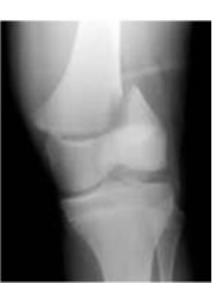

Q8/ What is the type of fracture shown in these pictures?

- A- Salter harris fracture II